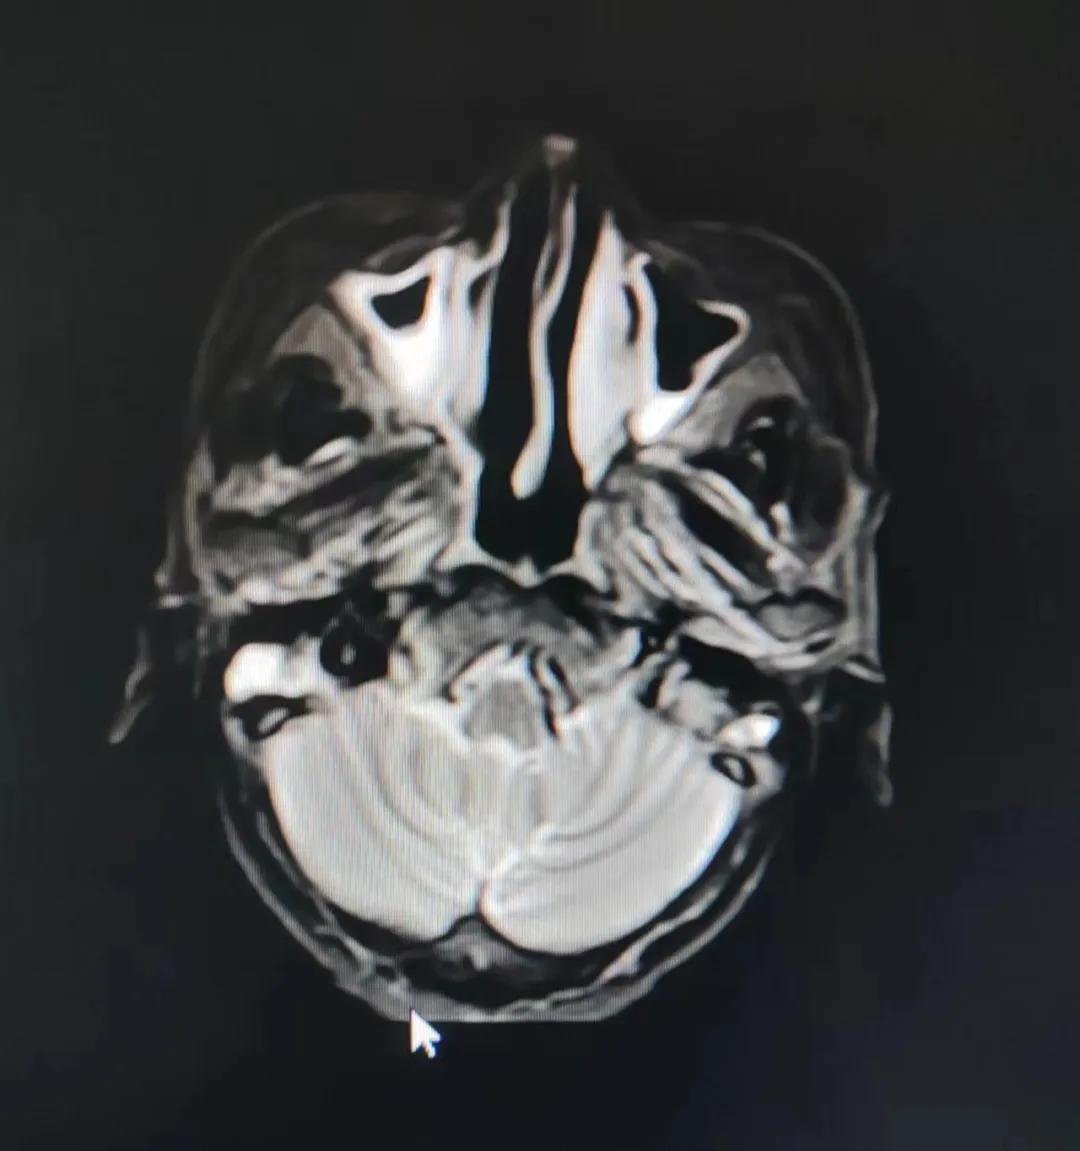

漯河市二院精準放療救治七旬鼻腔惡性淋巴瘤老人

70歲的彭阿姨,5個月前因鼻部瘙癢伴流血不止在當?shù)卦\所治療,瘙癢和出血癥狀不但沒有得到有效控制,反而進行性加重,并出現(xiàn)鼻腔堵塞、進食困難,經(jīng)外院病理活檢確診為“鼻腔惡性淋巴瘤”。不斷加重的病痛已嚴重影響了老人的生活質(zhì)量,為求診治,患者及家屬于今年2月份慕名來到了市二院放療科。

治療前

老人因鼻部腫物堵塞鼻腔并且侵犯鼻咽導致鼻塞、疼痛、吞咽困難,身心都備受煎熬,趙亮主任在詢問其病史期間幾度落淚。趙亮主任向患者及家屬解釋說:“現(xiàn)代放療比過去的傳統(tǒng)放療設備先進,技術不斷提升,能對腫瘤區(qū)域的照射劑量進行優(yōu)化,做到準確定位、精準照射,同時,最大限度地降低正常組織的受量,對全身情況影響很小。”

考慮到患者年齡較大、體質(zhì)差,手術難度大,且常規(guī)的放射治療難以保護患者晶體造成患者雙眼視力損傷,放療團隊以最快的速度制定了精準放射治療方案并開始為其實施治療。僅僅數(shù)日后,老人腫塊出血即得到控制,腫塊明顯縮小,放療20次后腫塊迅速縮??!

治療后

放療結束,除了放療處的皮膚輕微放射性皮炎外,基本沒有什么不良反應。復查發(fā)現(xiàn),鼻腔淋巴瘤已不可見,目前患者已康復出院。